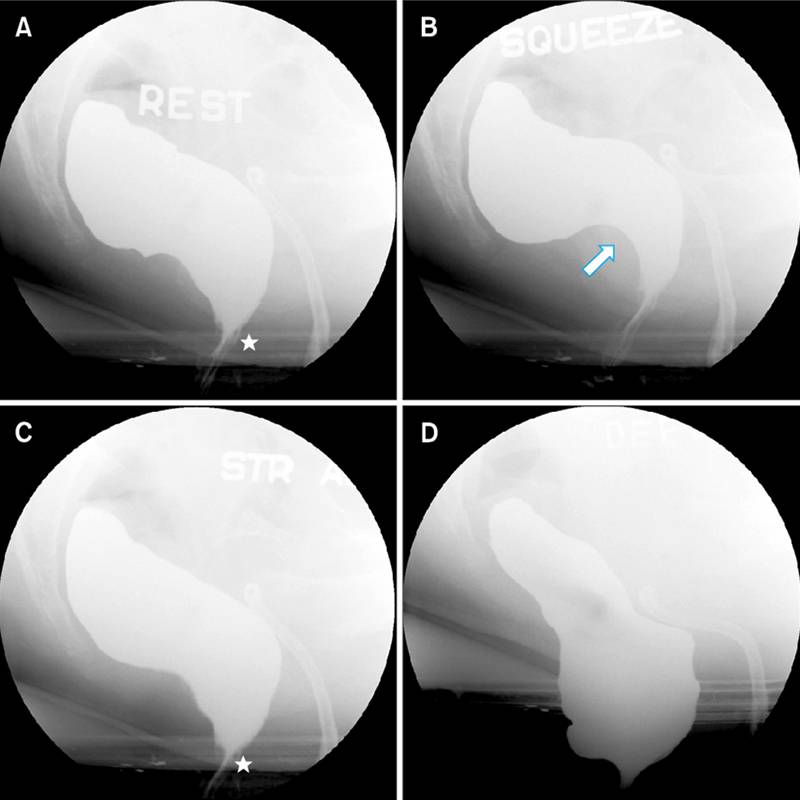

3. Дефекография — либо с помощью рентгена, либо с помощью МРТ. Пациенту в прямую кишку вводят рентгеноконтрастное вещество, и он пробует сходить в туалет. В это время ему делают МРТ или специальный рентген. Так врач видит, куда идет каловый комок, где он застревает, как продвигается, есть ли в кишке дополнительные карманы, полностью опорожняется кишка или нет.

Так выглядит нормальная дефекография. Источник: researchgate.net

А здесь есть проблемы с работой лобково-прямокишечной мышцы. Источник: researchgate.net